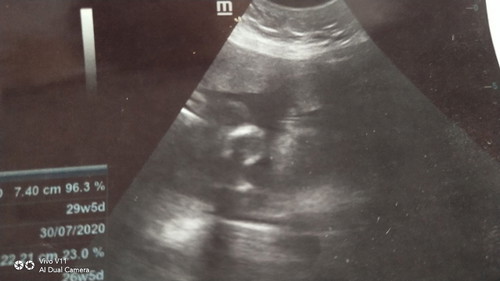

Aritu scan 27minggu doktor ckp nmpk cam girl..mula2 scan masa kandungan 3 4 bln doktor cakap boy..keliru ahh..sya serta kn gmbr..mana tahu da ibu2 yg arif mnengok nye..

Tak nampak sangat gambar scan tu😅